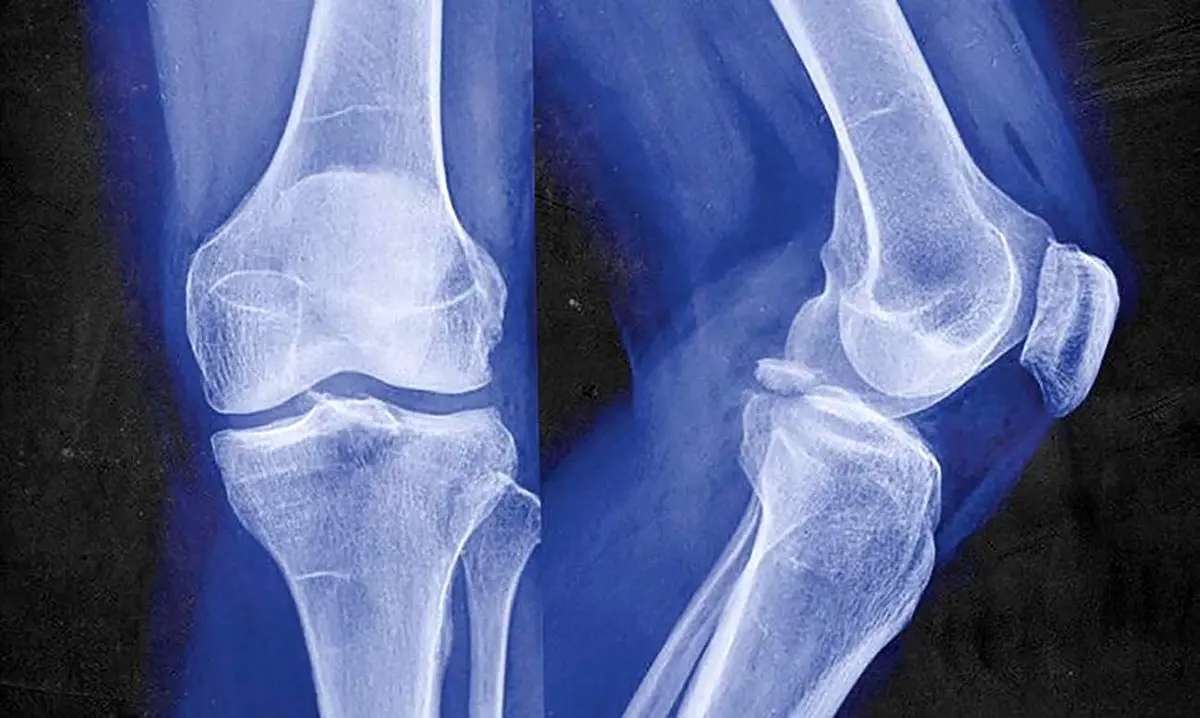

به گزارش خبرنگار اجتماعی رکنا، شکستگیهای استخوانی یکی از شایعترین آسیبهای فیزیکی در جهان است. طبق آمارهای موجود، حدود 15 تا 25 درصد از مردم در طول عمر خود حداقل یک بار دچار شکستگی استخوانی میشوند. این آمار بسته به منطقه جغرافیایی، سطح توسعهیافتگی و سن افراد ممکن است متفاوت باشد.

ناحیههای دست و پا بیشتر از سایر نقاط بدن در معرض شکستگی قرار دارند. شکستگی استخوانهای مچ دست، ساعد، و لگن به خصوص در افراد مسن بسیار شایع است. در بین نواحی بدن، شکستگی لگن به دلیل عوارض شدید و نیاز به مراقبتهای طولانیمدت پس از شکستگی، بیشترین نگرانی را ایجاد میکند. در مقابل، شکستگیهای استخوانهای دندهها و جمجمه نسبت به سایر نقاط بدن کمتر رخ میدهند و معمولاً در شرایط خاص و شدید مانند تصادفات رانندگی یا ضربههای سنگین مشاهده میشوند.